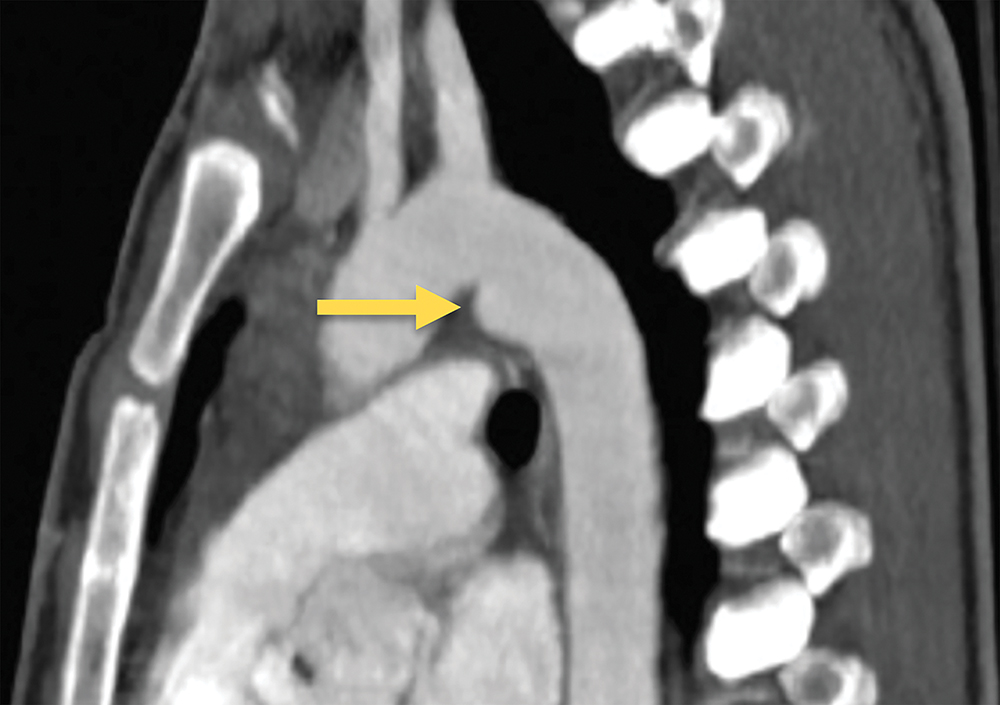

Multiple normal anatomic variants and conditions can mimic an acute TAI. Ductal remnants, a diverticulum or small bump, are normal remnants of the embryologic ductus arteriosus. Ductal remnants are typically smooth-walled and have obtuse margins that are continuous with the aortic wall and are often calcified ( Fig. 24.6 ).

Multiple anatomic variants can mimic an acute TAI. Ductal remnants, a diverticulum or small bump, are normal remnants of the embryologic ductus arteriosus. Typically smooth walled, ductal remnants (arrow) have obtuse margins that are continuous with the aortic wall and often calcified.

In contrast, the typical pseudoaneurysm forms an irregular outpouching from the lumen, displaying acute margins and intimal irregularity at its base. Another variant that might mimic aortic injury is the aortic spindle, which is a narrow and dilated area of the aorta between the left subclavian and the ductus arteriosus. Infundibula can have a similar appearance to a ductal remnant but are found at the origin of bronchial or intercostal arteries and can also be confused with a small pseudoaneurysm. Infundibula are typically cone-shaped and smooth-walled, with a small artery extending from the apex. However, in all these normal variants, the contour is smooth and regular without intimal irregularities. If a definitive diagnosis is in question, other specific imaging modalities, such as TEE, are helpful to eliminate any confusion and confirm the diagnosis.